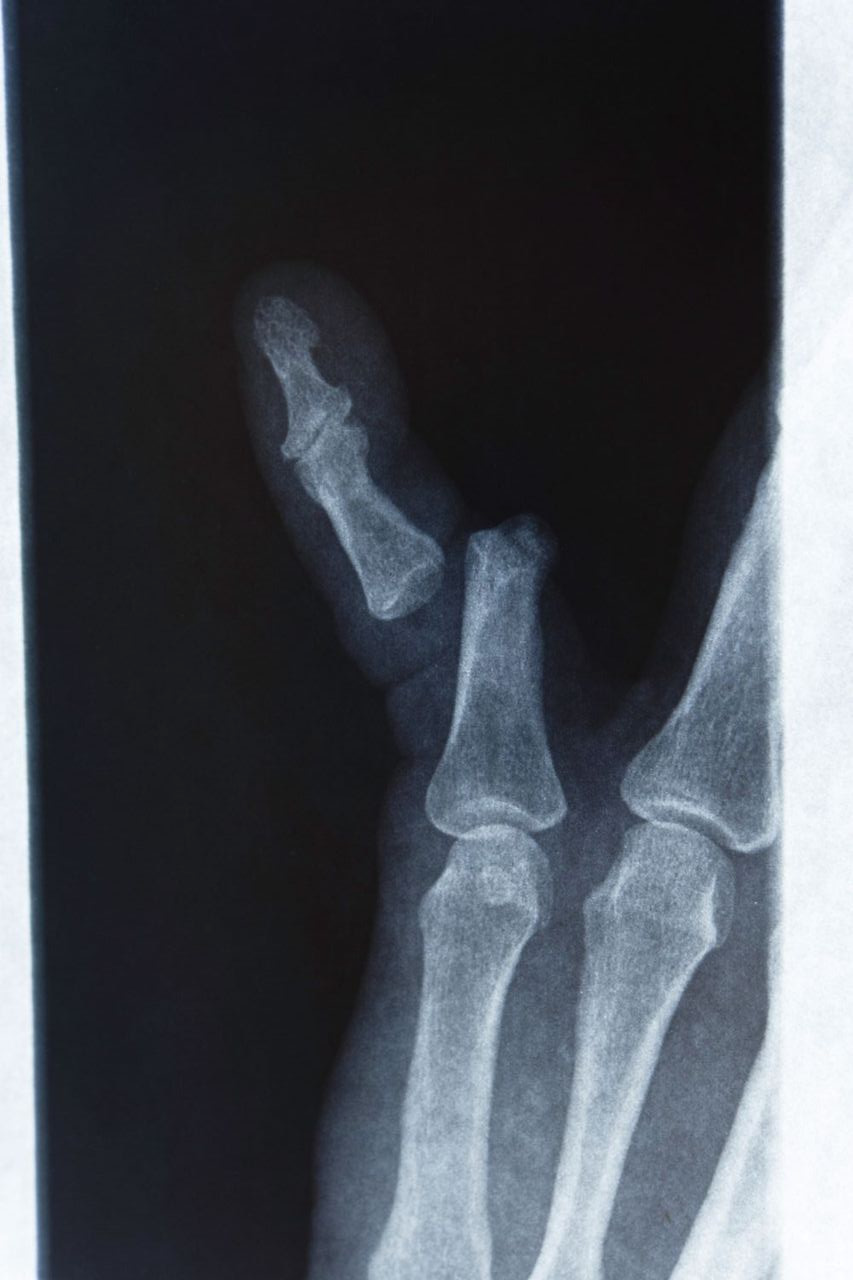

발가락만큼이나 손가락 역시 일상에서 쉽게 골절이 발생하는 부위입니다. 손가락 골절은 대개 손을 이용해 무거운 물건을 받치거나, 야구‧배구 같은 스포츠 활동 중 충격을 받았을 때 생깁니다. 손가락은 정교한 동작을 수행해야 하므로, 치료와 재활 과정이 특히 중요합니다.

깁스 vs 스플린트 vs 핀 고정 수술

- 핀 고정 수술

- 뼈가 복합적으로 부러지거나, 어긋나서 그대로 붙으면 기능에 치명적 문제가 예상되는 경우에는 핀이나 금속판을 삽입하는 수술을 진행합니다.

- 수술 후에는 손가락 움직임을 최소화하고, 적절한 시점에 재활 운동을 시작해야 합니다.